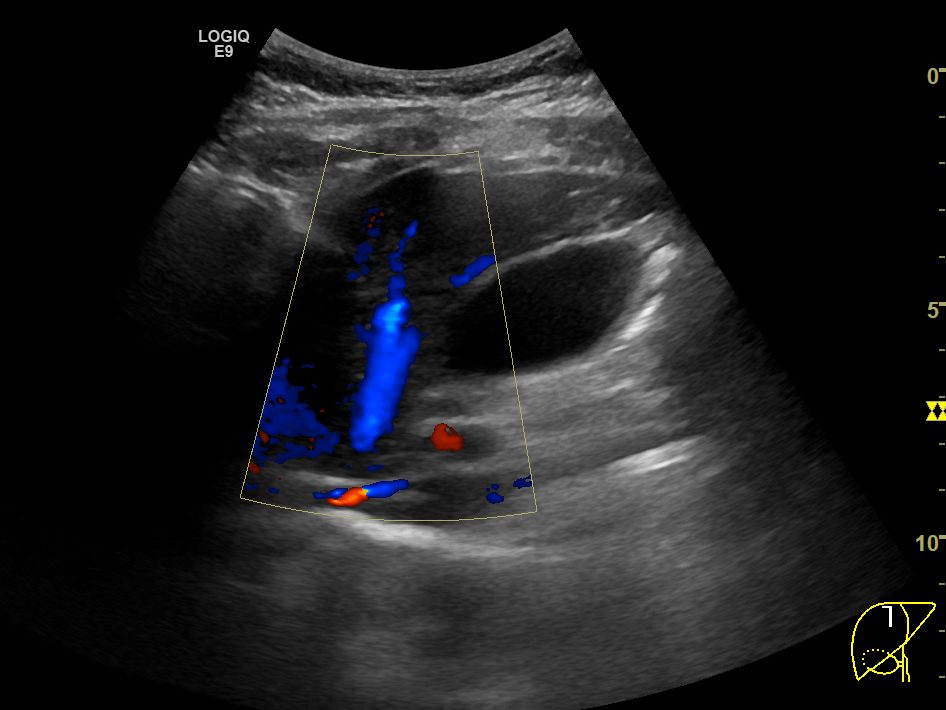

다음으로 중간정맥(middle hepatic vein)의 B모드 및 컬러도플러영상입니다. 컬러도플러영상에서 또렷하게 보이는 중간정맥이 B모드영상에서는 마찬가지로 매우 가늘고 희미하게 보입니다. 컬러도플러 영상에서 보여주는 중간정맥의 굵기가 실제 직경과는 차이가 있겠으나, B모드에서 보이는 것보다는 훨씬 직경이 클 것으로 보이며, B모드영상에서는 전혀 확인할 수 없었던 가지부분들도 컬러도플러영상에서는 또렷하게 확인됩니다.

B모드영상에서 간정맥이 실제보다 훨씬 얇고 희미하게 보이거나, 아예 잘 보이지 않는 이유는 간정맥의 혈관벽이 얇아서 초음파신호가 반사되지 않아 영상에서 혈관벽을 특정할 수 없기 때문입니다. 특히 간실질의 에코음영이 거칠거나 간섬유화가 심하게 진행된 만성 간질환 환자들에서 간정맥을 확인하지 못하거나, 굉장히 가늘게 보이는 경우가 많습니다.

위의 영상들은 모두 GE사의 logiq E9 장비를 통해 얻은 영상입니다. 혹시 몰라 tissue harmonic image모드를 꺼놓거나, 다른 영상옵션들을 조절해봐도, 간정맥이 실제보다 가늘거나 희미하게 보이는 환자분들에서 일반적인 B모드영상보다 간정맥을 더 또렷하게 보여주는건 불가능했습니다. 지난 17년 내내 GE사의 초음파장비만을 써와서 타사 장비들의 상황을 비교해보지 못했지만, 어쨋던 GE사의 장비들 만큼이라도 이런 한계점을 극복해서 더 나은 영상을 담보할 수 있게 발전했으면 좋겠습니다.

그런 장비의 발전과 진보가 있기 전까지는 간초음파의 표준영상을 얻는 과정에서 간정맥, 특히 우간정맥의 장축을 보여주는 영상을 촬영할 때에는 좀 더 번거롭더라도, 컬러도플러영상을 함께 촬영하면서 우간정맥을 확인하는 것도 좀 더 신뢰할만한 간초음파영상을 얻기 위해 권장될 수 있겠다는 생각입니다.